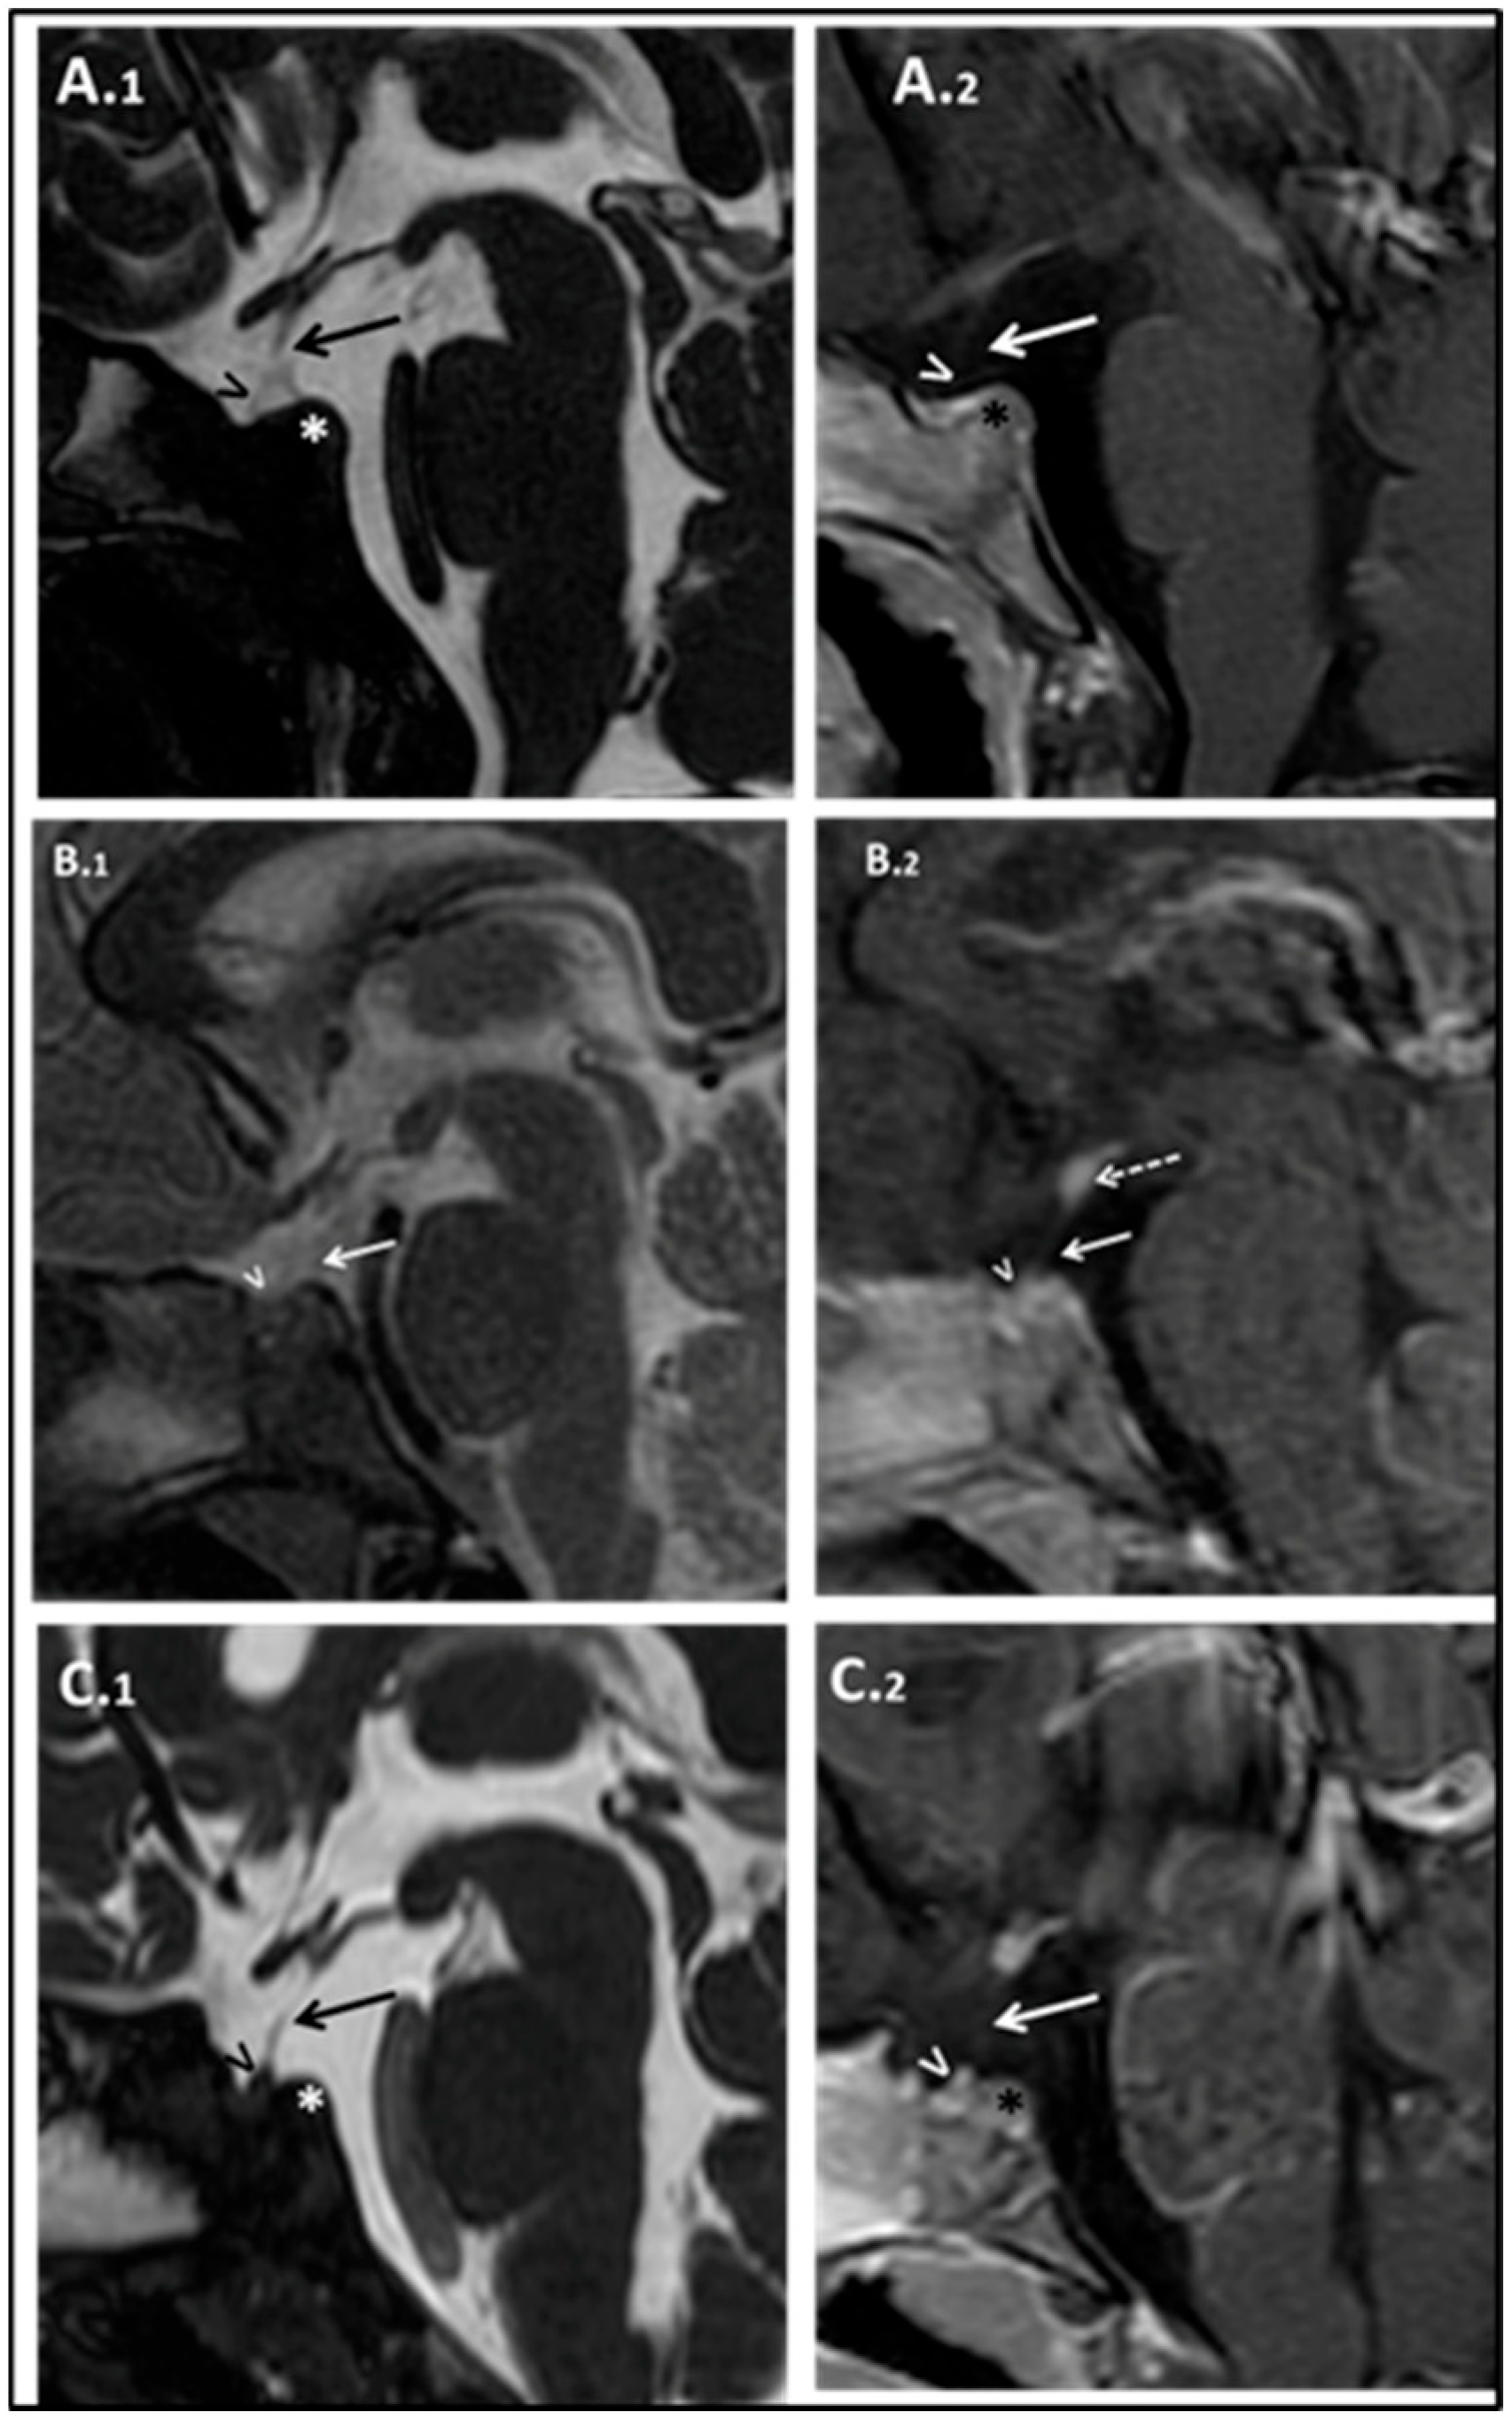

At 17 months of age, his length was 68.5 cm (−2 SD), and his weight was 8.17 Kg (−2 SD); the HC was normal. No facial dysmorphisms were present. Psychomotor development was normal. IGF1 was confirmed lower than normal: 7.1 ng/mL (−2.31 SD). According to the diagnostic guidelines for GH deficiency in children under 2 years of age, a brain MRI was suggested, yet parents initially refused the sedation procedure needed to perform the exam. Thus, we performed an arginine stimulation test that confirmed the suspicion of GH deficiency: peak GH of 1.18 ng/mL. Other pituitary hormones were still within the normal range (Supplementary Materials, Table S1). Subsequently, parents agreed to perform the brain MRI that documented poorly developed sella turcica, marked anterior pituitary hypoplasia, pituitary stalk interruption, and ectopic posterior pituitary (Figure 3A.1,A.2).

Figure 3. Patient’s brain MRI studies. A.III.1’s Sagittal MRI images T2 weighted (A.1) and T1 weighted with gadolinium (A.2). Subject B.III.2. Sagittal MRI images T2 weighted (B.1), and T1 weighted with gadolinium (B.2). B.III.3 Brain MRI. Sagittal MRI images T2 weighted (C.1) and T1 weighted with gadolinium (C.2). Hypoplastic anterior pituitary lobe (indicated by “>”), small poorly developed sella turcica (indicated by “*”), absent pituitary stalk (see the “arrow”), and ectopic posterior pituitary located at the level of the median eminence.

Complete hormonal screening revealed low levels of IGF1 (21.23 ng/mL; −2.48 SD) (see Supplementary Materials, Table S2). A growth hormone stimulation test confirmed severe GH deficiency (GH peak after arginine and GHRH stimulation of 5.8 ng/mL and 2.7 ng/mL, respectively). Brain MRI imaging evidenced the triad, hypoplastic anterior pituitary gland, thin pituitary stalk, and ectopic posterior pituitary gland, along with poorly developed sella turcica (see Figure 3B.1,B.2).

Patient B.III.3 was born at term with a weight of 2200 gr (−2.09 SD), a length of 38 cm (−4.28 SD), and an HC of 32 cm (−1.56 SD). Similarly to the sister, he did not present postnatal catch-up growth, so at 9 months, weight and length were already below the 3rd centile, and he was first referred to a pediatric endocrinologist. At 16 months of age, he received a diagnosis of GH deficiency due to a persistent low level of IGF1 (14.7 ng/mL; −1.83 SD, r.v.: 14–203 ng/mL) during symptomatic hypoglycemia. At that time, he was 70 cm tall (−3.96 SD), below his mid-parental height (164 cm; −2.14 SD); his weight was 7.520 kg (−3.04 SD), and his BMI was 15.35 kg/m2 (−0.80 SD). A brain MRI scan depicted hypoplastic anterior pituitary gland, thin pituitary stalk, and ectopic posterior pituitary gland (see Figure 3C.1,C.2). Moreover, poorly developed sella turcica and olfactory bulbs and tract hypoplasia–agenesia were retrieved.